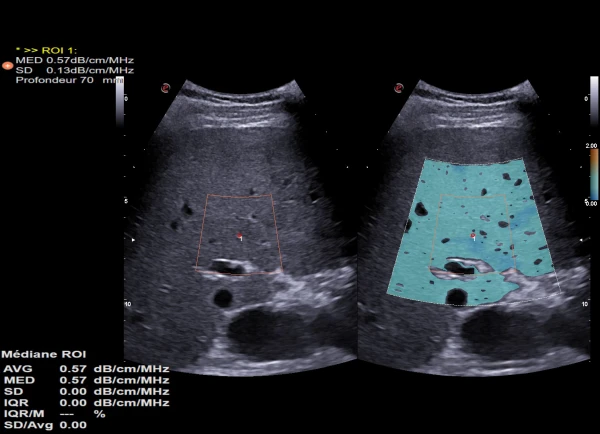

Ko'krak massasini tahlil qilish. Qiziqarli sohada sut bezlari o'smalarini tasniflash bo'yicha avtomatik taklif;